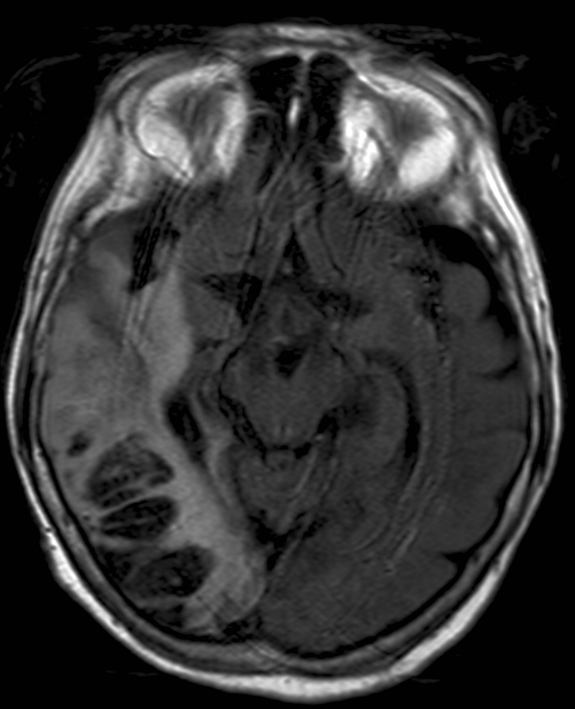

All three types of intracranial hematoma can occur as a result of head trauma:

• Subdural bleeding is caused by injured bridging veins (elongation, tears) e.g. when a sudden deceleration occurs. This type of injury generally is not associated with a fracture.

5. A middle aged chronic alcoholic male. On unenhanced CT a typical crescent shape subdural hemorrhage is seen on both sides. Because of its etiology it extends across suture lines.

• Contusion hemorrhage occurs upon sudden deceleration (e.g. car accident - collision) when the brain parenchyma due to its inertness keeps moving and hits the cranial bone. Frequently, contusion develops on the opposite side as well, since on an abrupt stop the brain collides with the bone than bounces off and hits the opposite wall of the skull. (coup - contrecoup effect)

7. Elderly female was suffered a direct hit in the parietal region. Coronal reconstruction of a unenhanced CT scan: At the site of the impact on the right side parietally a typical lens shaped epidural hematome is formed. On the opposite side in the temporal lobe at the contrecoup contusion site parenchymal bleeding is seen